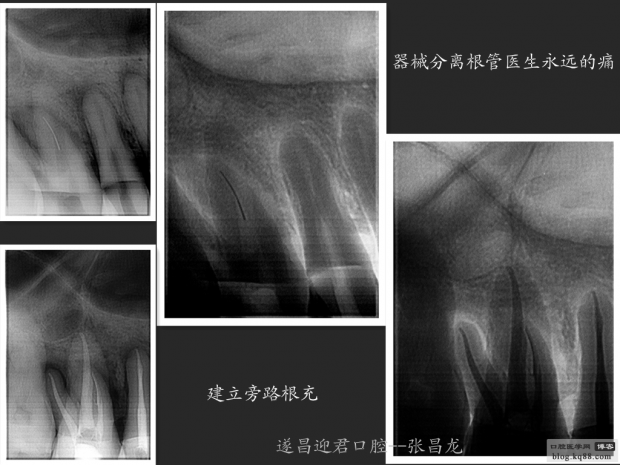

每個(gè)牙科醫(yī)生都不愿碰到器械分離,但常在河邊走,哪有不濕鞋的,我想大部分醫(yī)生根管治療中都發(fā)生過(guò)器械分離吧。在此就不在累贅那些造成根管器械分離的原因,醫(yī)生們也都知道那些。遇到器械分離莫慌,我們還是有挽救的余地。由于醫(yī)生的技術(shù)原因,設(shè)備原因,不是每個(gè)斷針都能取出來(lái)的。與對(duì)一部分?jǐn)噌樜覀兛梢試L試建立旁路通道,斷針與根管壁之間的間隙慢慢通入到工作長(zhǎng)度,然后常規(guī)根管治療。

14,15根管治療

根管斷針牙科醫(yī)生永遠(yuǎn)的痛。小心操作,遠(yuǎn)離斷針。